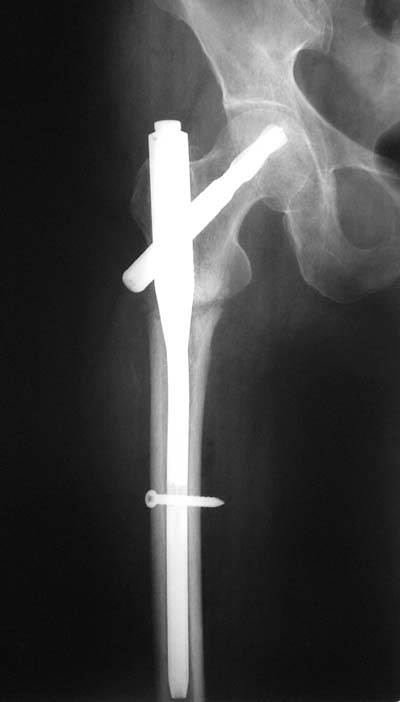

Да? Качество рентгенограмм конечно неочень, но ведь это нестабильный перелом 31.А2.2, не так ли?

Не думаю так. см вложение.

> Не думаю так. см вложение.